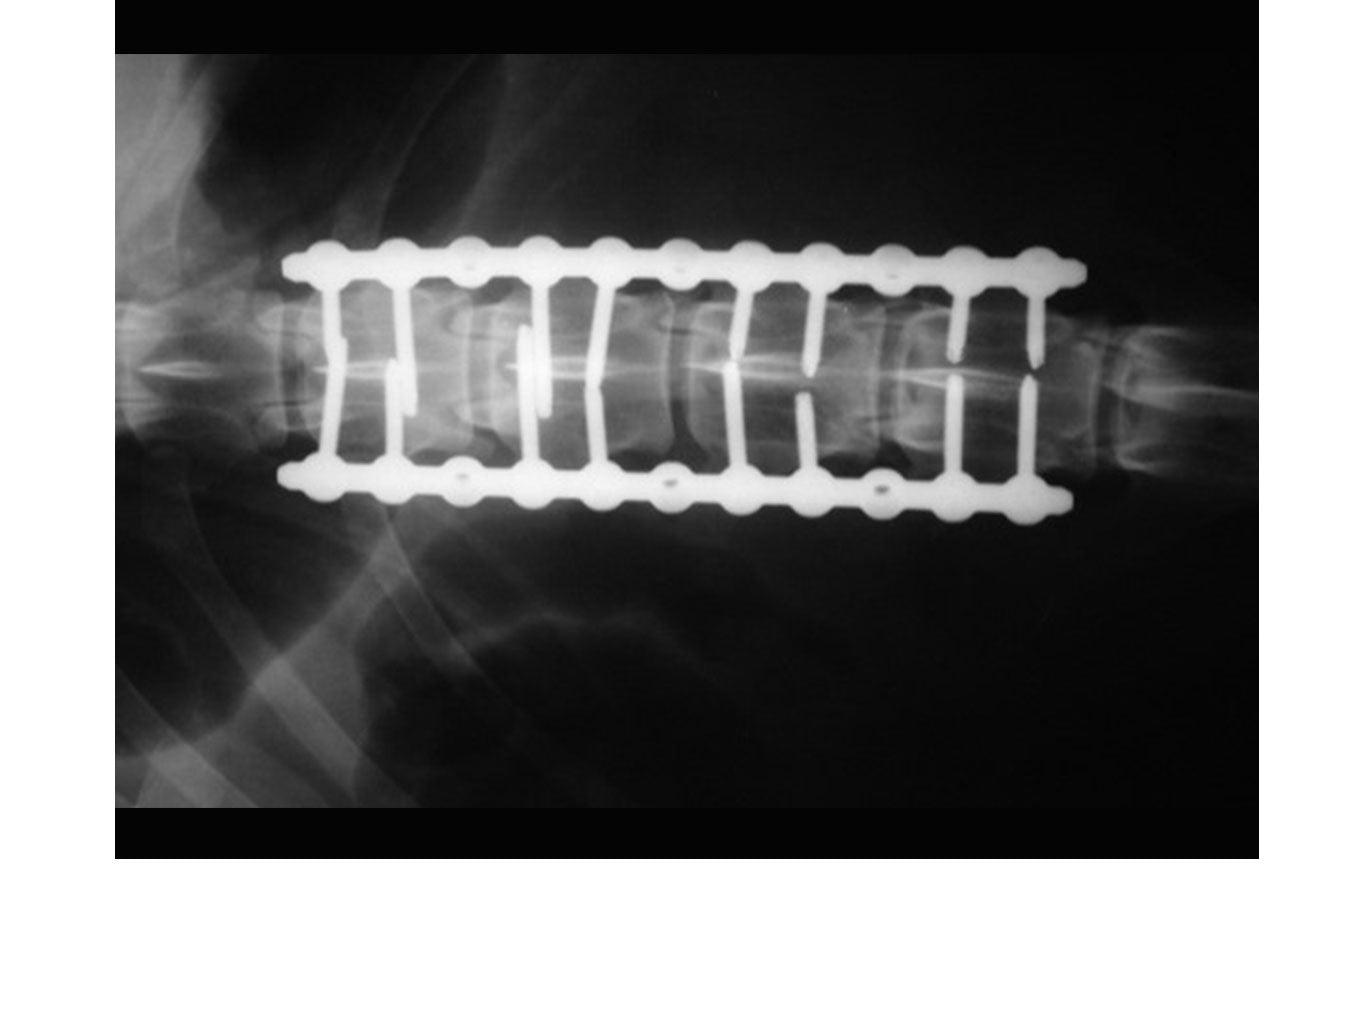

• Thoracic, T-L Lumbar

• Lumbo-sacral

SOP™ uniquely offers a spinal stabilization system with reasonable cost. The SOP™ plates are commonly used in pairs with the screws engaging vertebral pedicles or bodies. The SOP™ can be used similarly to a pedicle screw system for the thoracolumbar spine, or as a locking anterior system for cervical stabilisation/fusions.

// User Cases

Highlighting the cases of these products in real-life situations is vital to demonstrating their success. Below are cases studies of long-term follow up surgeries.